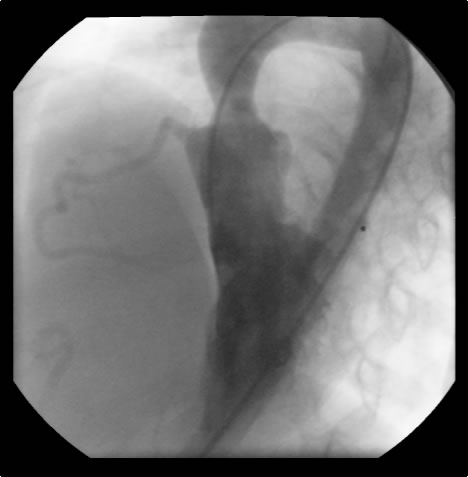

An asymptomatic, 5-year-old, 18-kg boy known by genetic testing to have Williams syndrome on physical examination had a IV/VI harsh systolic ejection murmur and no diastolic murmur. Preoperative echocardiogram showed an aortic root dimension of 2 cm and the dimension at the level of stenosis in the ascending aorta was 8 mm. Peak echocardiogram gradient was 70 mm Hg with a cardiac catheterization gradient of 50 mm Hg. The child had no peripheral pulmonary artery stenosis.

Preoperative transesophageal echocardiogram in long-axis view shows ascending aorta with aortic valve to the left. The markers indicate the aoritc root dimension to be 2.0 cm and hte mid portion of the stenosis to be 0.8 cm.